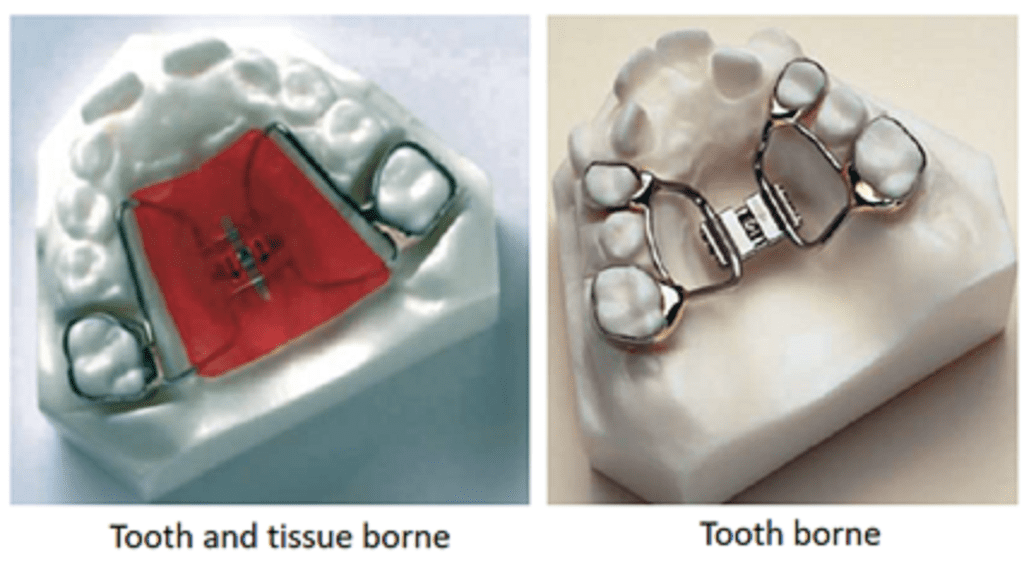

- Tooth-borne or Tooth and Tissue-Borne Type

Removable RME Appliances

The appliance basically consists of a screw in the midline with retentive claps on the posterior teeth. The acrylic plate is split in the middle and activations of the screw forces the two halves to move apart, resulting in the desired expansion.

This appliance is more effective when used in the early mixed dentition phase. Its efficiency in the late mixed dentition and older patients is suspect because of the ossification of the mid-palatal suture and the resulting delay in splitting causes the retention of the appliance to get compromised. Patient compliance is paramount to all removable appliances. Efficiency is less compared to fixed.

Fixed RME Appliances

Fixed rapid maxillary expansion appliances are fixed expanders which cannot be removed by the patient. The fixed RME appliances can be either tooth-borne or tooth and tissue-borne.

Tooth-borne appliances: Isaacson type or the Hyrax type of appliance

Tooth and tissue-borne appliances: Derichsweiler or the Hass type of appliances